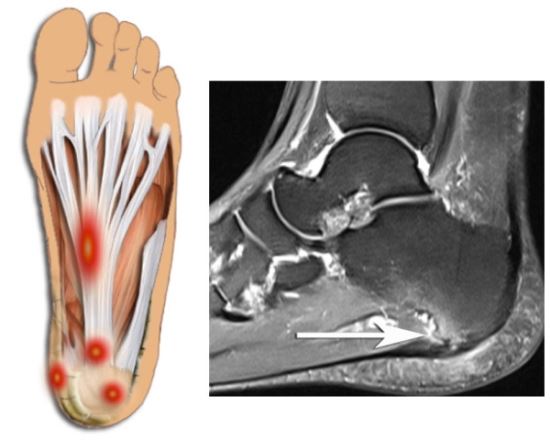

아킬레스건염

- 아킬레스건의 염증으로 인해 발생하는 통증으로, 발뒤꿈치와 발바닥 사이의 연결 부위에 통증이 느껴질 수 있습니다. 주로 격렬한 운동 후, 혹은 운동 부족 후 갑자기 운동을 시작할 때 자주 발생합니다. 통증은 특히 아침에 일어났을 때나 활동을 시작할 때 더 심해질 수 있습니다.